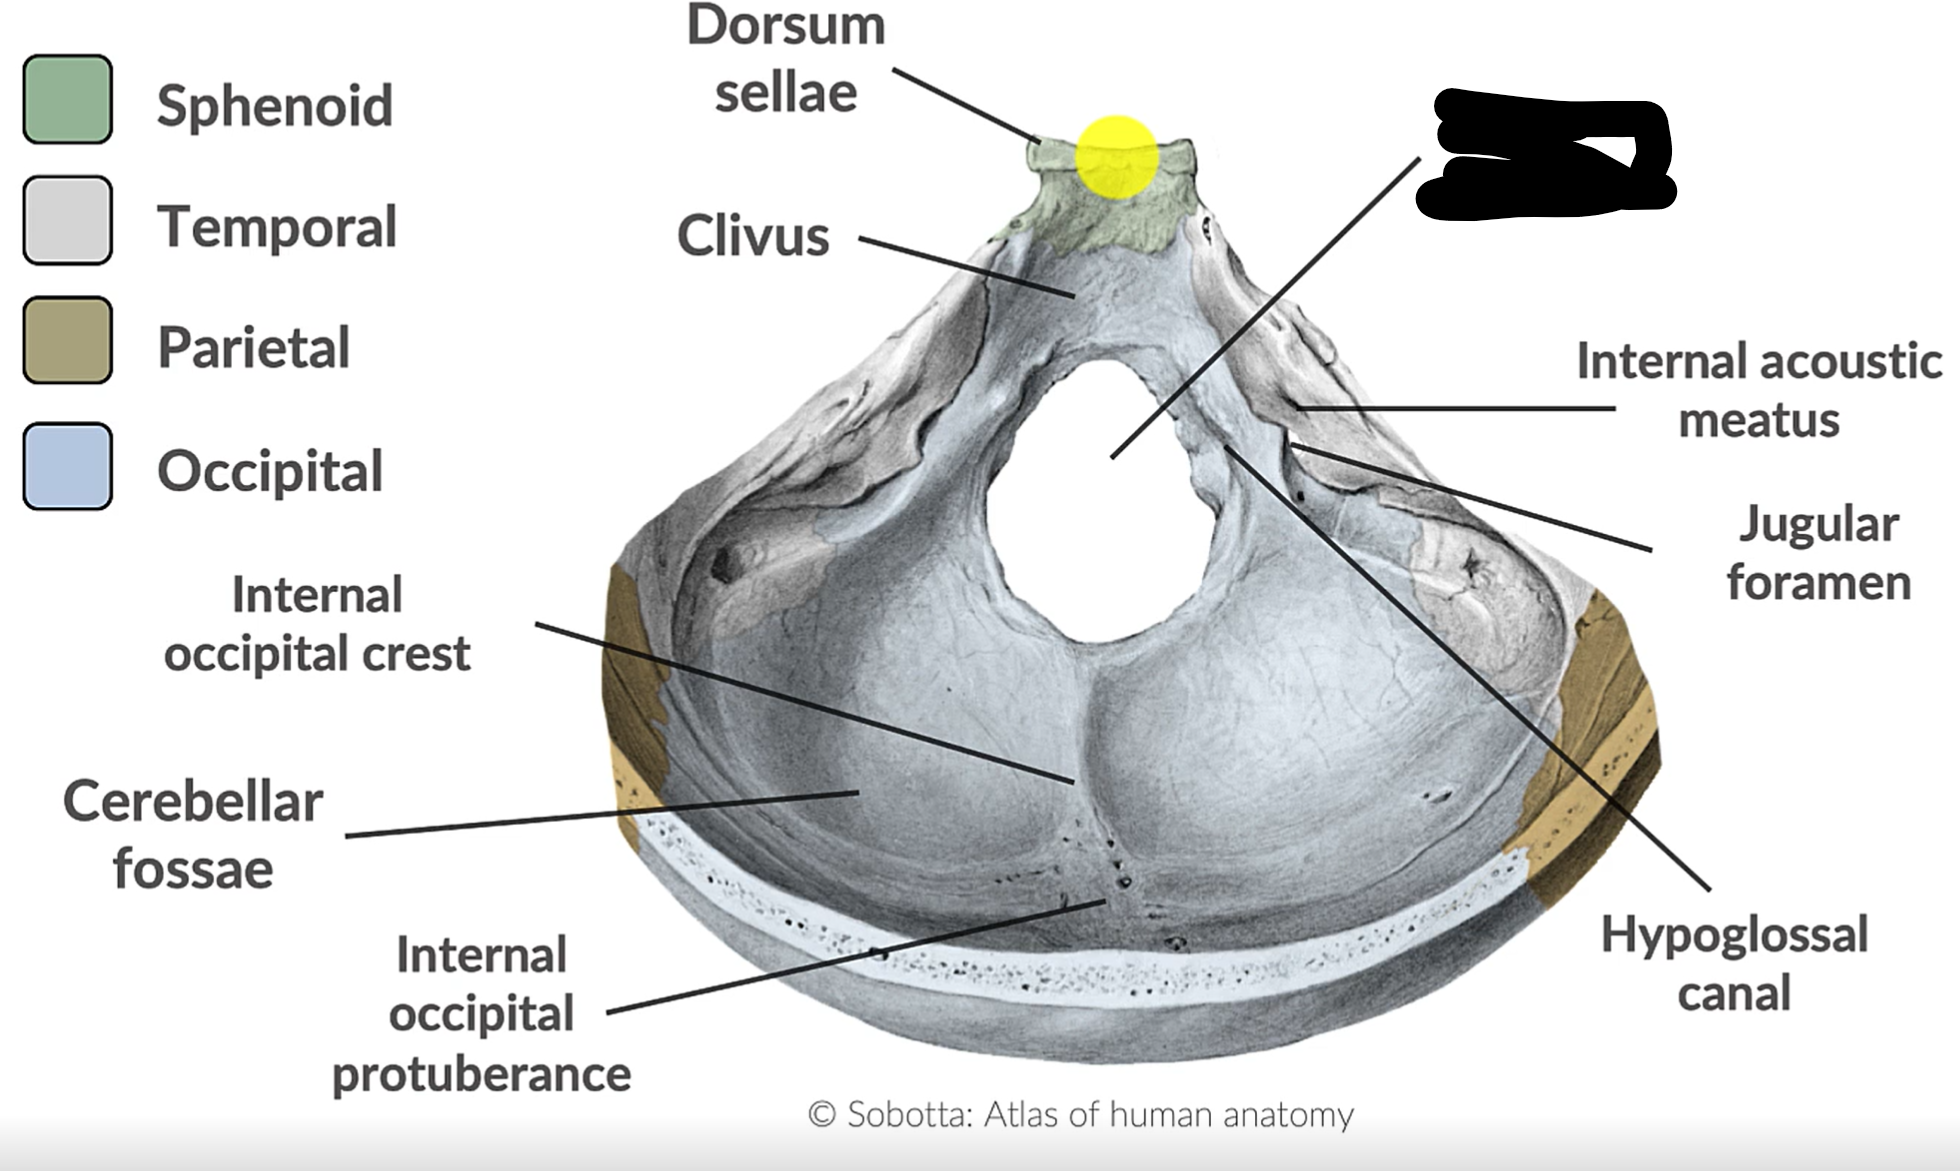

What forms the posterior cranial fossa?

Occipital, temporal, parietal and sphenoid bones

Foramen magnum

Jugular foramen

Internal acoustic mediatus

Hypoglossal canal